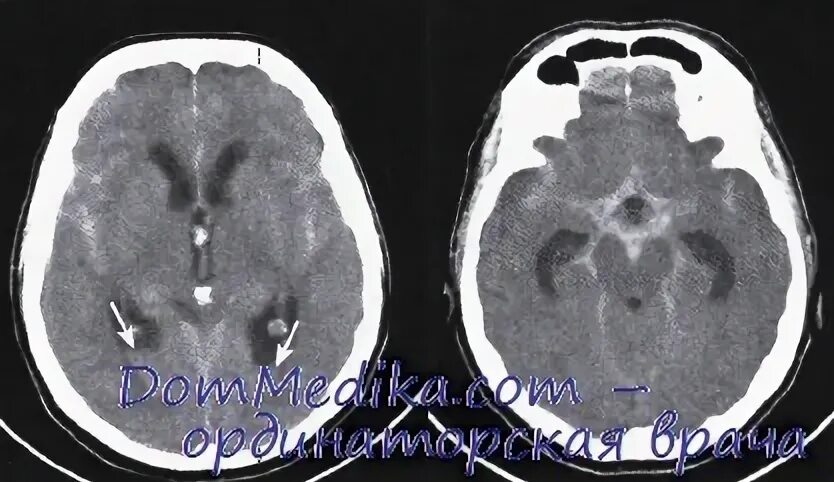

Умеренно выраженной наружной гидроцефалии у взрослых